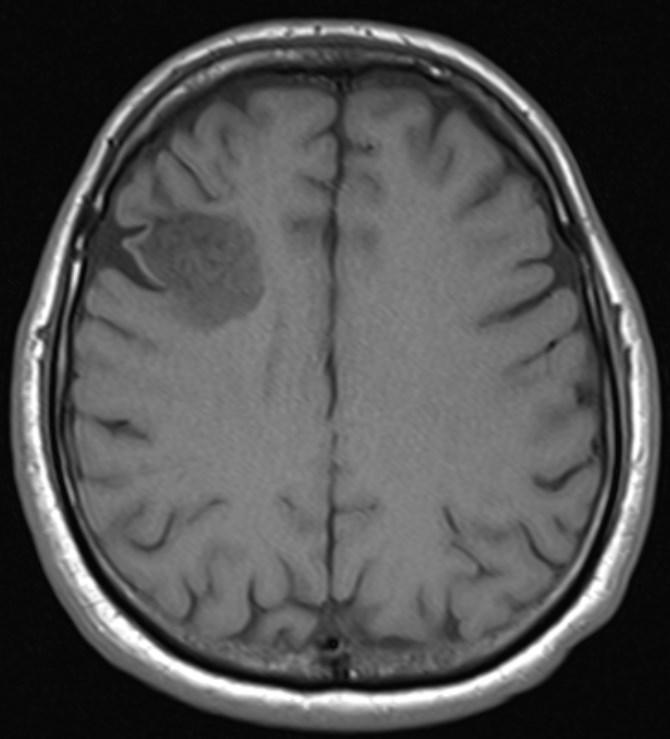

Answer: Primary hydatid cyst of right frontal lobe.

MR images revealed Gharbi type V hydatid cysts in right frontal lobe.

Gharbi classified hydatid cyst ultrasonographic images into 5 types: Type 1, walled, unilocular, anechoic; type 2, separated membranes; type 3, multisepta, daughter vesicles; type 4, heterogenic, hypo-hyperechogenic; type 5, calcification of a section of the wall or completely calcified (4). The cysts characteristically have three components: Pericyst, Exocyst, and Endocyst.